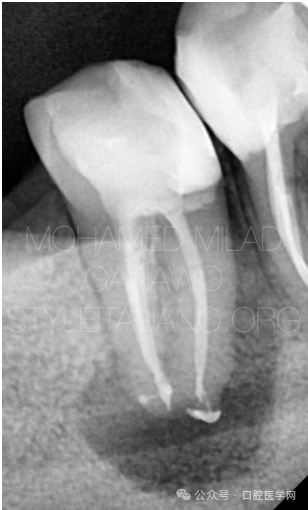

图4

充填后即刻显微镜下影像,可见C形根管的充填形态。

图5

根管充填完成,可见侧支根管显影。